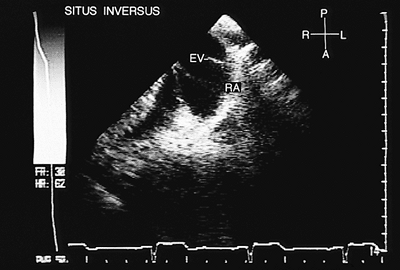

Situs Inversus

In situs inversus, the right-sided appendage has the characteristics of an anatomically left appendage (Fig. 8.2.7), whereas the left-sided appendage has the characteristics of an anatomically right appendage (Fig. 8.2.8). The atrial cavity on the right is connected to the pulmonary veins (Fig. 8.2.9), whereas the atrial cavity on the left is connected to the venae cavae and receives the coronary sinus. When contrast studies are performed, the atrial chamber situated on the left is opacified (Fig. 8.2.10). The eustachian valve can be recognized in the atrium situated on the left (Fig. 8.2.11). The connection of the suprahepatic veins to the inferior vena cava and its drainage into the atrium situated on the left can be observed in transgastric recordings (Fig. 8.2.12).

FIGURE 8.2.11. Situs inversus. The right atrium (RA), situated on the left, is identified by the presence of the eustachian valve (EV)